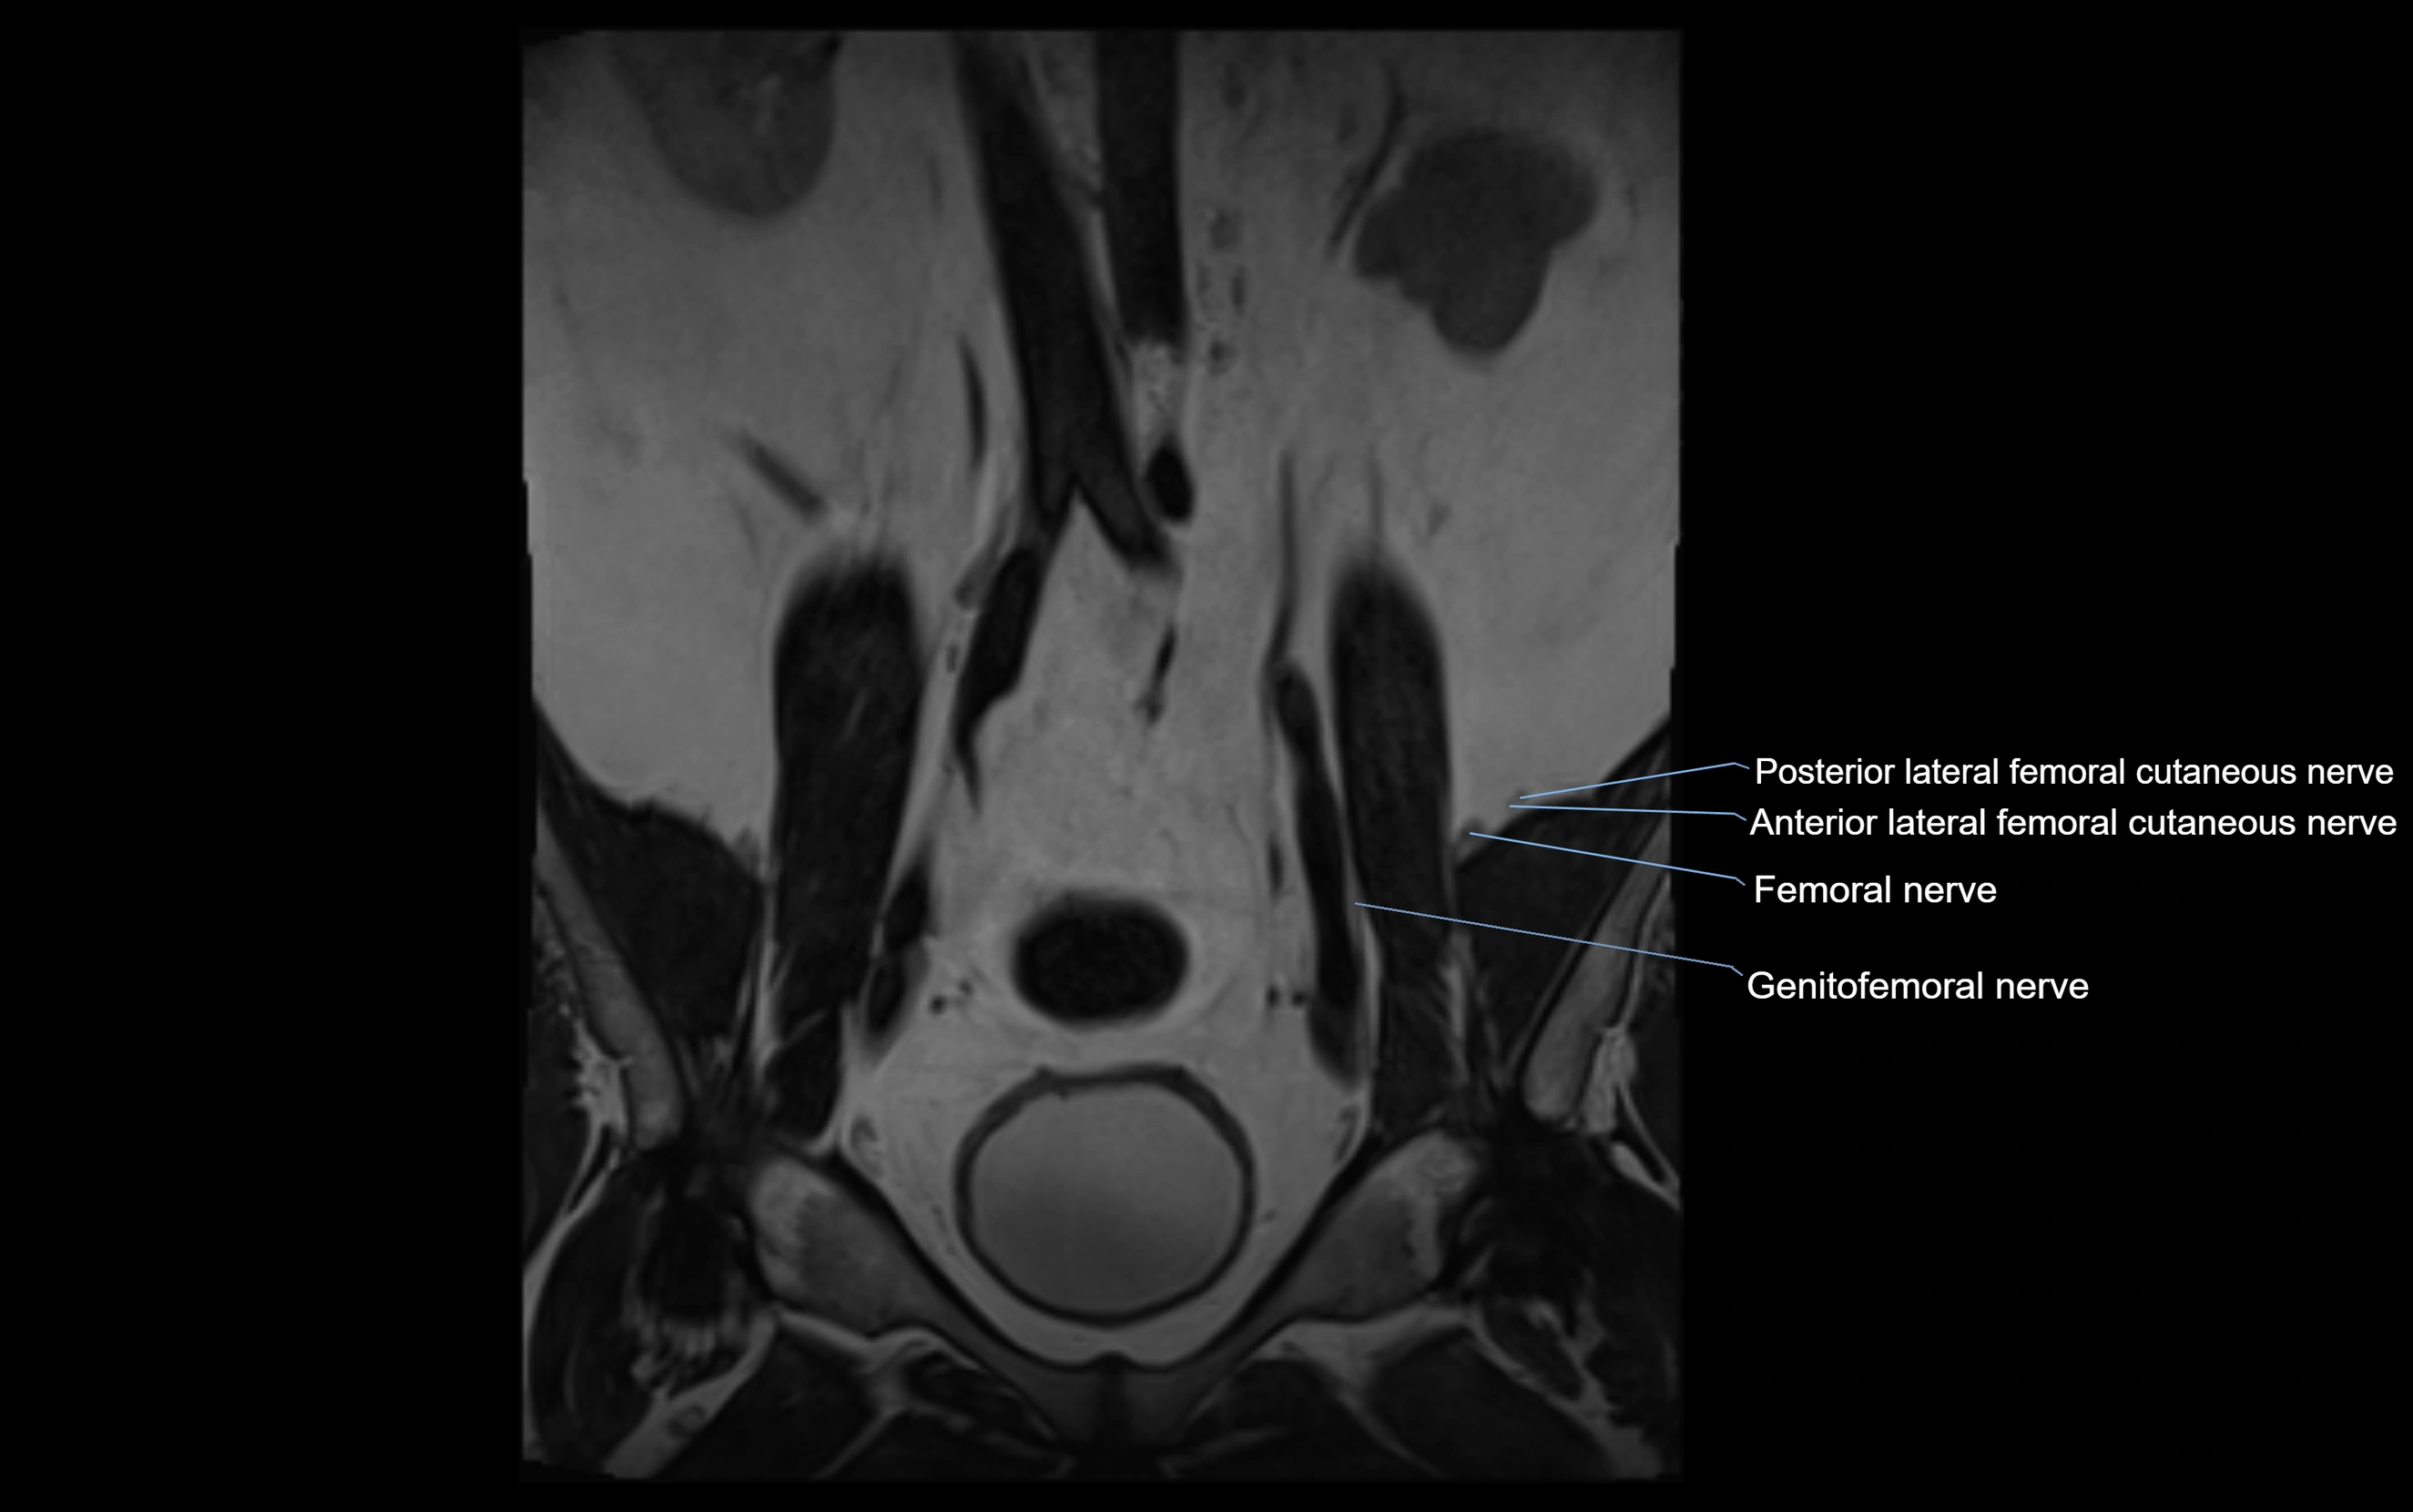

MRI Appearance

T1-weighted images:

• Nerve appears as a very thin low-to-intermediate signal intensity structure

• Surrounded by bright fat, aiding visualization

T2-weighted images:

• Nerve shows intermediate to mildly hyperintense signal compared to muscle

• Pathological involvement appears brighter

STIR (Short Tau Inversion Recovery):

• Normal nerve appears dark

• Inflamed or entrapped nerve appears bright hyperintense

T1 Fat-Sat Post-Contrast:

• Normal nerve enhances minimally

• Pathologic nerve (neuritis, entrapment, tumor infiltration) shows focal or diffuse enhancement

3D T2 SPACE / CISS:

• Nerve appears intermediate to mildly hyperintense compared to muscle

• Surrounded by bright fat or CSF, improving visualization

• Best sequence for mapping small pelvic nerves such as the anococcygeal